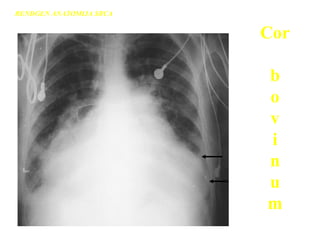

Rtg pluća i srca – normalan nalazRtg pluća i srca – normalan nalaz

Cor

b

o

v

i

n

u

m

RENDGEN ANATOMIJA SRCA